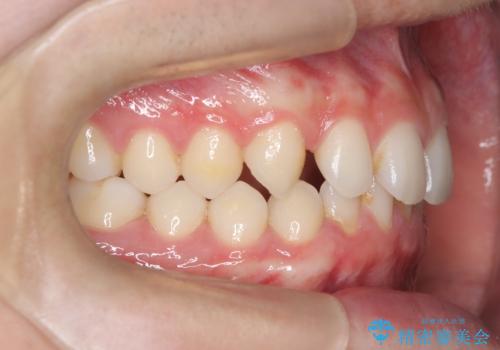

- 主訴:上の歯列の空隙を閉じたい

上顎前歯部に空隙が目立ちました。ワイヤー矯正、インビザライン(マウスピース矯正)どちらの方法でも適用症例と説明し、ワイヤー矯正治療(審美装置)を希望されました。

上顎歯列の空隙を閉じるのと一緒に、ディープバイト気味の被蓋も下顎前歯の圧下を行い改善しました。